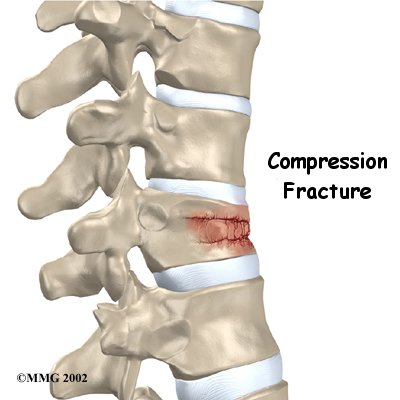

Compression fractures are the most common type of fracture affecting the spine. A compression fracture of a spine bone (vertebra) causes the bone to collapse in height.

Compression fractures are commonly the result of osteoporosis. About 700,000 cases of compression fractures due to osteoporosis occur each year in the United States. Spinal bones that are weakened from osteoporosis may become unable to support normal stress and pressure. As a result, something as simple as coughing, twisting, or lifting can cause a vertebra to fracture.

An injury to the spine, such as from a hard fall on the buttocks or blow to the head, can cause a spinal compression fracture. Compression fractures may also occur if cancer from other parts of the body spreads to the spine. Cancer weakens the spinal bones and makes them prone to fractures.

Compression fractures cause this section of bone to collapse. When the fracture is due to osteoporosis, it usually occurs in the lower part of the thoracic spine, near the bottom of the rib cage.

Strong, healthy bones are able to withstand the forces and strains of normal activity. Compression fractures in the spine happen when either the forces are too great or the bones of the spine aren't strong enough. The vertebral body cracks under pressure. Fractures from forceful impact on the spine tend to crack the back (posterior) part of the vertebral body. Fractures from osteoporosis usually occur in the front (anterior) part of the vertebral body.

is a disease that weakens bone. Sometimes the bones in the spine weaken to the point that even mild forces can lead to a compression fracture. A simple action like reaching down to pull on a pair of socks can cause a weakened vertebra to fracture. The front of the vertebra (the part closest to the front of the body) crumbles, causing the round vertebral body to become wedge-shaped. This angles the spine forward, producing a hunch-backed appearance, called kyphosis.

Compression fractures caused by thin, weakened bones may cause little or no pain at first. Sometimes pain is centered over the area where the fracture has occurred. The collapsed vertebra gives the spine a hunched appearance, and the loss of vertebral height shortens the muscles on each side of the spine. This forces the back muscles to work harder, causing muscle fatigue and pain. When pain does occur, it usually goes away after a few weeks. However, back pain sometimes escalates to the point that patients seek medical help.

Traumatic compression fractures can produce intense pain in the back that spreads into the legs. If the fracture severely damages the vertebral body, bone fragments may lodge in the spinal canal, pressing on the spinal cord. This can paralyze muscles and impair sensation in the areas supplied by the damaged nerve tissue. Such a fracture may also cause the spine to become unstable. When this happens, the spine eventually tilts forward into increased kyphosis, and the potential grows for future complications with the spinal cord.